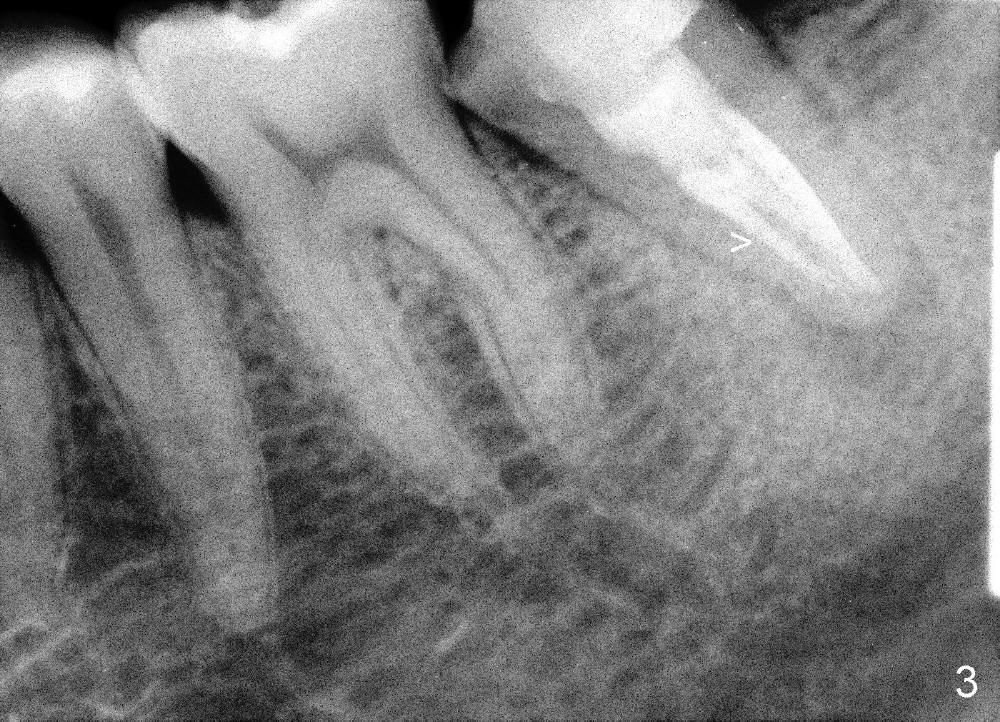

冷先生四五年前来诊所诊治,左下第二磨牙(图一:18)做过根管治疗,牙冠,偶尔不适,近中牙冠不密和(*,open margin),估计迟早会脱落,到时再重做根管治疗(retreat)好像为此不晚,病人听了这个方案没意见。三年半过去了,一切如旧,左下第二磨牙根尖阴影仍存在(图二*),仿佛一个根管没充填(箭头),病人同意拔除左上智齿(图一,四:16)。又过半年左下牙冠终于脱落,病人自动要求重做根管治疗,没充填根管找到,充填(图三箭头),之后症状消失,他很高兴。

为什么那个牙冠会脱落呢?本来第二磨牙垂直高度就不足,另外似乎对合牙(图一,:15)向下面伸长(箭头),占据下牙空间,牙冠高度不够,最好方法便是使用微型植牙(图五箭头)和橡皮筋(*),持续对对合牙施加压力,它慢慢地往上移动(intrusion)。刚四十岁的冷先生对新鲜事物容易接受,正好他的保险还保这项治疗(局部矫正)。两个月后,牙齿移位不少(图六),总共四个月我们目的达到了(开始做牙冠):其实矫枉过正(图七),正是我们期待,不过告诉实验室做牙冠时不必使用所有间隙,让对合牙自己下降。